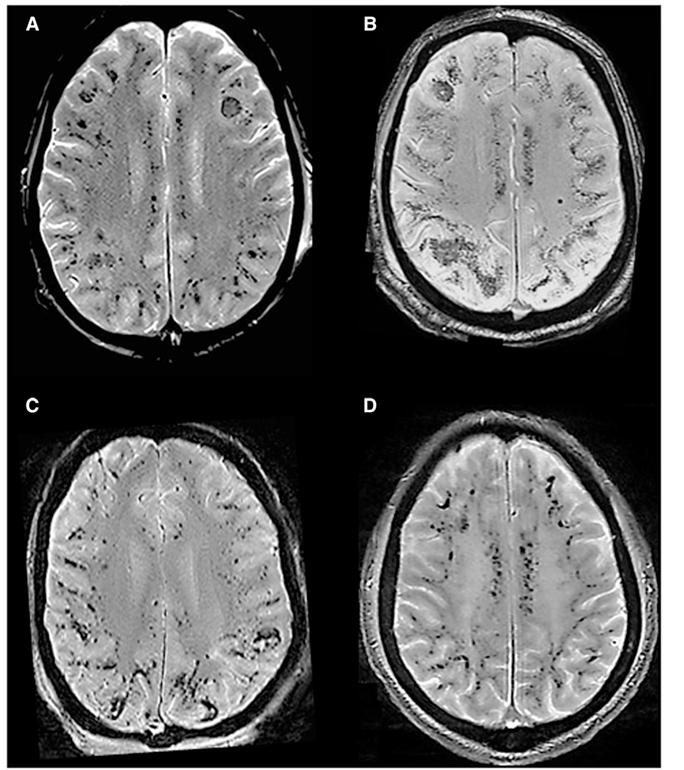

DIC SWI示双侧大脑半球、小脑及脑干弥漫性CMBs